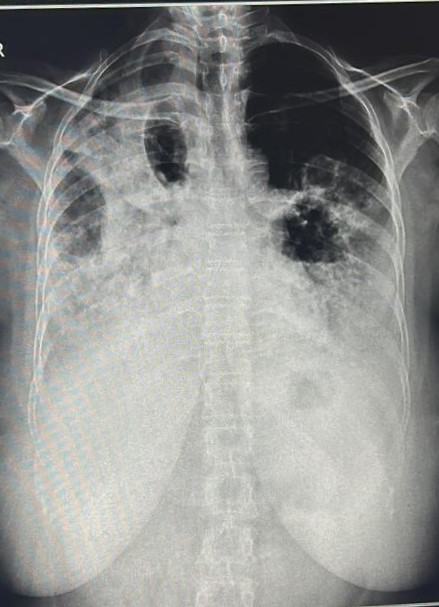

| 201 | IGGMC, Nagpur, Nagpur | P2 | 29-4271 | BUSHRA KHAN | Consent taken on Paper | 21 Yrs. |

Provisional Diag : PTB?

Final Diag : RIGHT SIDED CLINICALLY DIAGNOSED TUBERCULAR PLEURAL EFFUSION |

TB Case (Confirmed) | RIGHT SIDED PLEURAL EFFUSION | Abnormality visible on x-ray |